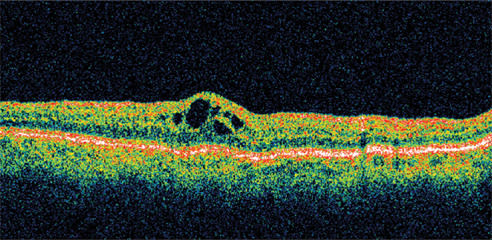

Figure 1. A 78-year-old woman complained of reduced visual acuity and contrast sensitivity OD 5 weeks after cataract surgery. Her presenting visual acuity was 20/40. Her IOP was 23 mm Hg, and retinal thickness was 478 μm on OCT.

A 78-year-old woman, with a history of cataract surgery, complained of reduced visual acuity and contrast sensitivity OD 5 weeks following surgery. She had a history of increased IOP, thought to be associated with steroid use, requiring medication following cataract surgery in the fellow eye. Her postoperative medication regimen consisted of a lowdose steroid taper.

Presenting visual acuity was 20/40. Her IOP was 23 mm Hg and retinal thickness was 478 μm on OCT (Figure 1). She was treated with nepafenac qid for 6 weeks and tapered over the ensuing 6 weeks. Her vision improved to 20/25 by 1 month with significant reduction in her retinal thickness (Figure 2). By 12 weeks, her visual acuity had improved to 20/20 with a retinal thickness of 216 μm and a normal foveal contour. This represents a reduction in retinal thickness of 262 μm from her pretreatment status (Figure 3). However, she continued to report a mild reduction in contrast sensitivity.